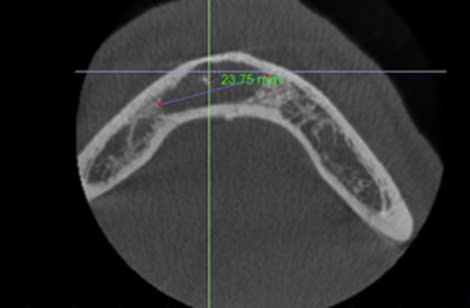

Quá trình lành thương, sửa chữa các mô quanh răng là một quá trình tái tạo phức tạp liên quan đến xương, dây chằng nha chu và xi măng. Các vùng mất khoáng hoà dần dần được lấp đầy bởi xương và cho hình ảnh cản quang nhiều hơn trên xquang. Nếu bản xương vỏ bị phá huỷ, quá trình lành thương sẽ bắt đầu từ việc tái tạo bản xương mặt ngoài và diễn ra hướng tâm, có nghĩa là lành thương từ ngoại vi về trung tâm [10]

Hình 2. Phim CBCT sau 12 tháng, bệnh nhân Đ.Q.Q